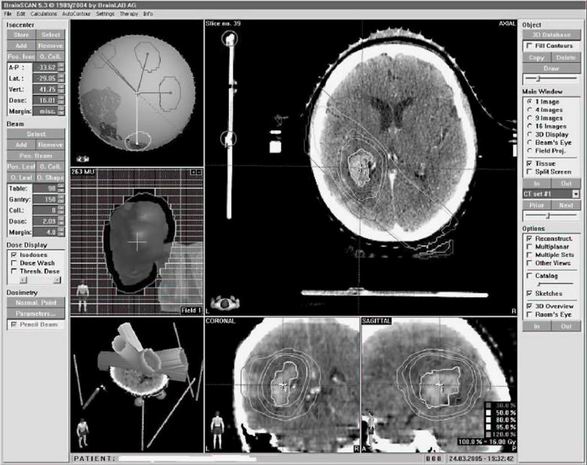

Ke snížení procenta komplikací je dnes nutné využít 3D plánování pomocí CT vyšetření a označení všech kritických orgánů

– jater, kontralaterální ledviny, míchy apod. Velmi důležitá je definice cílového objemu, vhodné je využití chirurgických klipů označujících lůžko ledviny. Samozřejmostí je rovněž výpočet objemové dávky jednotlivých orgánů (histogram dávka/objem). Tím významně eliminujeme procento komplikací radioterapie, kterým byly zatíženy historické studie. Stein a spol. uvádí snížení komplikací u skupiny 56 pacientů léčených pooperační radioterapií v dávce 46 Gy na 5 % (pouze u 3 pacientů z celkového počtu 56 nemocných).